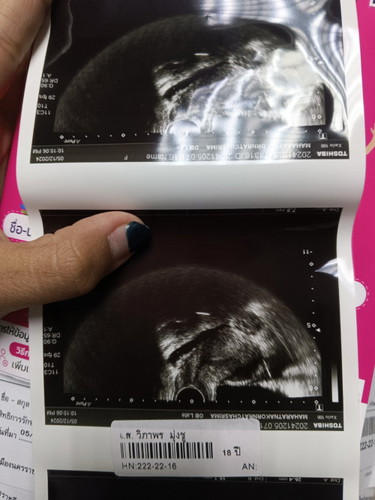

ท้อง2 ยังไม่เห็นภุงการตั้งครรภ์ค่ะ

4+3ฝาก ไม่เห็นถุงค่ะ เเต่คนเเรกเห็นถุงตอน4+5 จะเห็นไหมคะ อีก2สัปดาห์ #เเชร์ประสบการณ์กันจ้า

ของเราไปซาวด์คนที่ 2 มา 6 week เห็นถุงว่าอยู่ในมดลูก แต่ยังไม่เห็นตัวค่ะ ตอนท้องแรกเห็นตัวน้องตอน 8 week